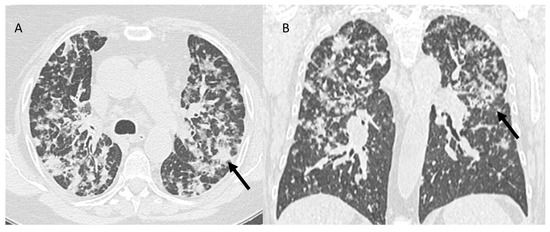

| RRP | Target area | Ground-glass opacities and consolidative opacities. | Unknown (A non-immune fixed drug reaction-like condition, dysregulated release of reactive oxygen species, abnormalities of tissue vasculature and impaired DNA repair). |

| RP | Target area | Ground-glass opacities and consolidative opacities. | Direct damage to the DNA and indirect damage through the production of reactive oxygen species (ROS), causing changes in vascularity and capillary permeability, activation of the inflammatory response and alteration of immunological response |